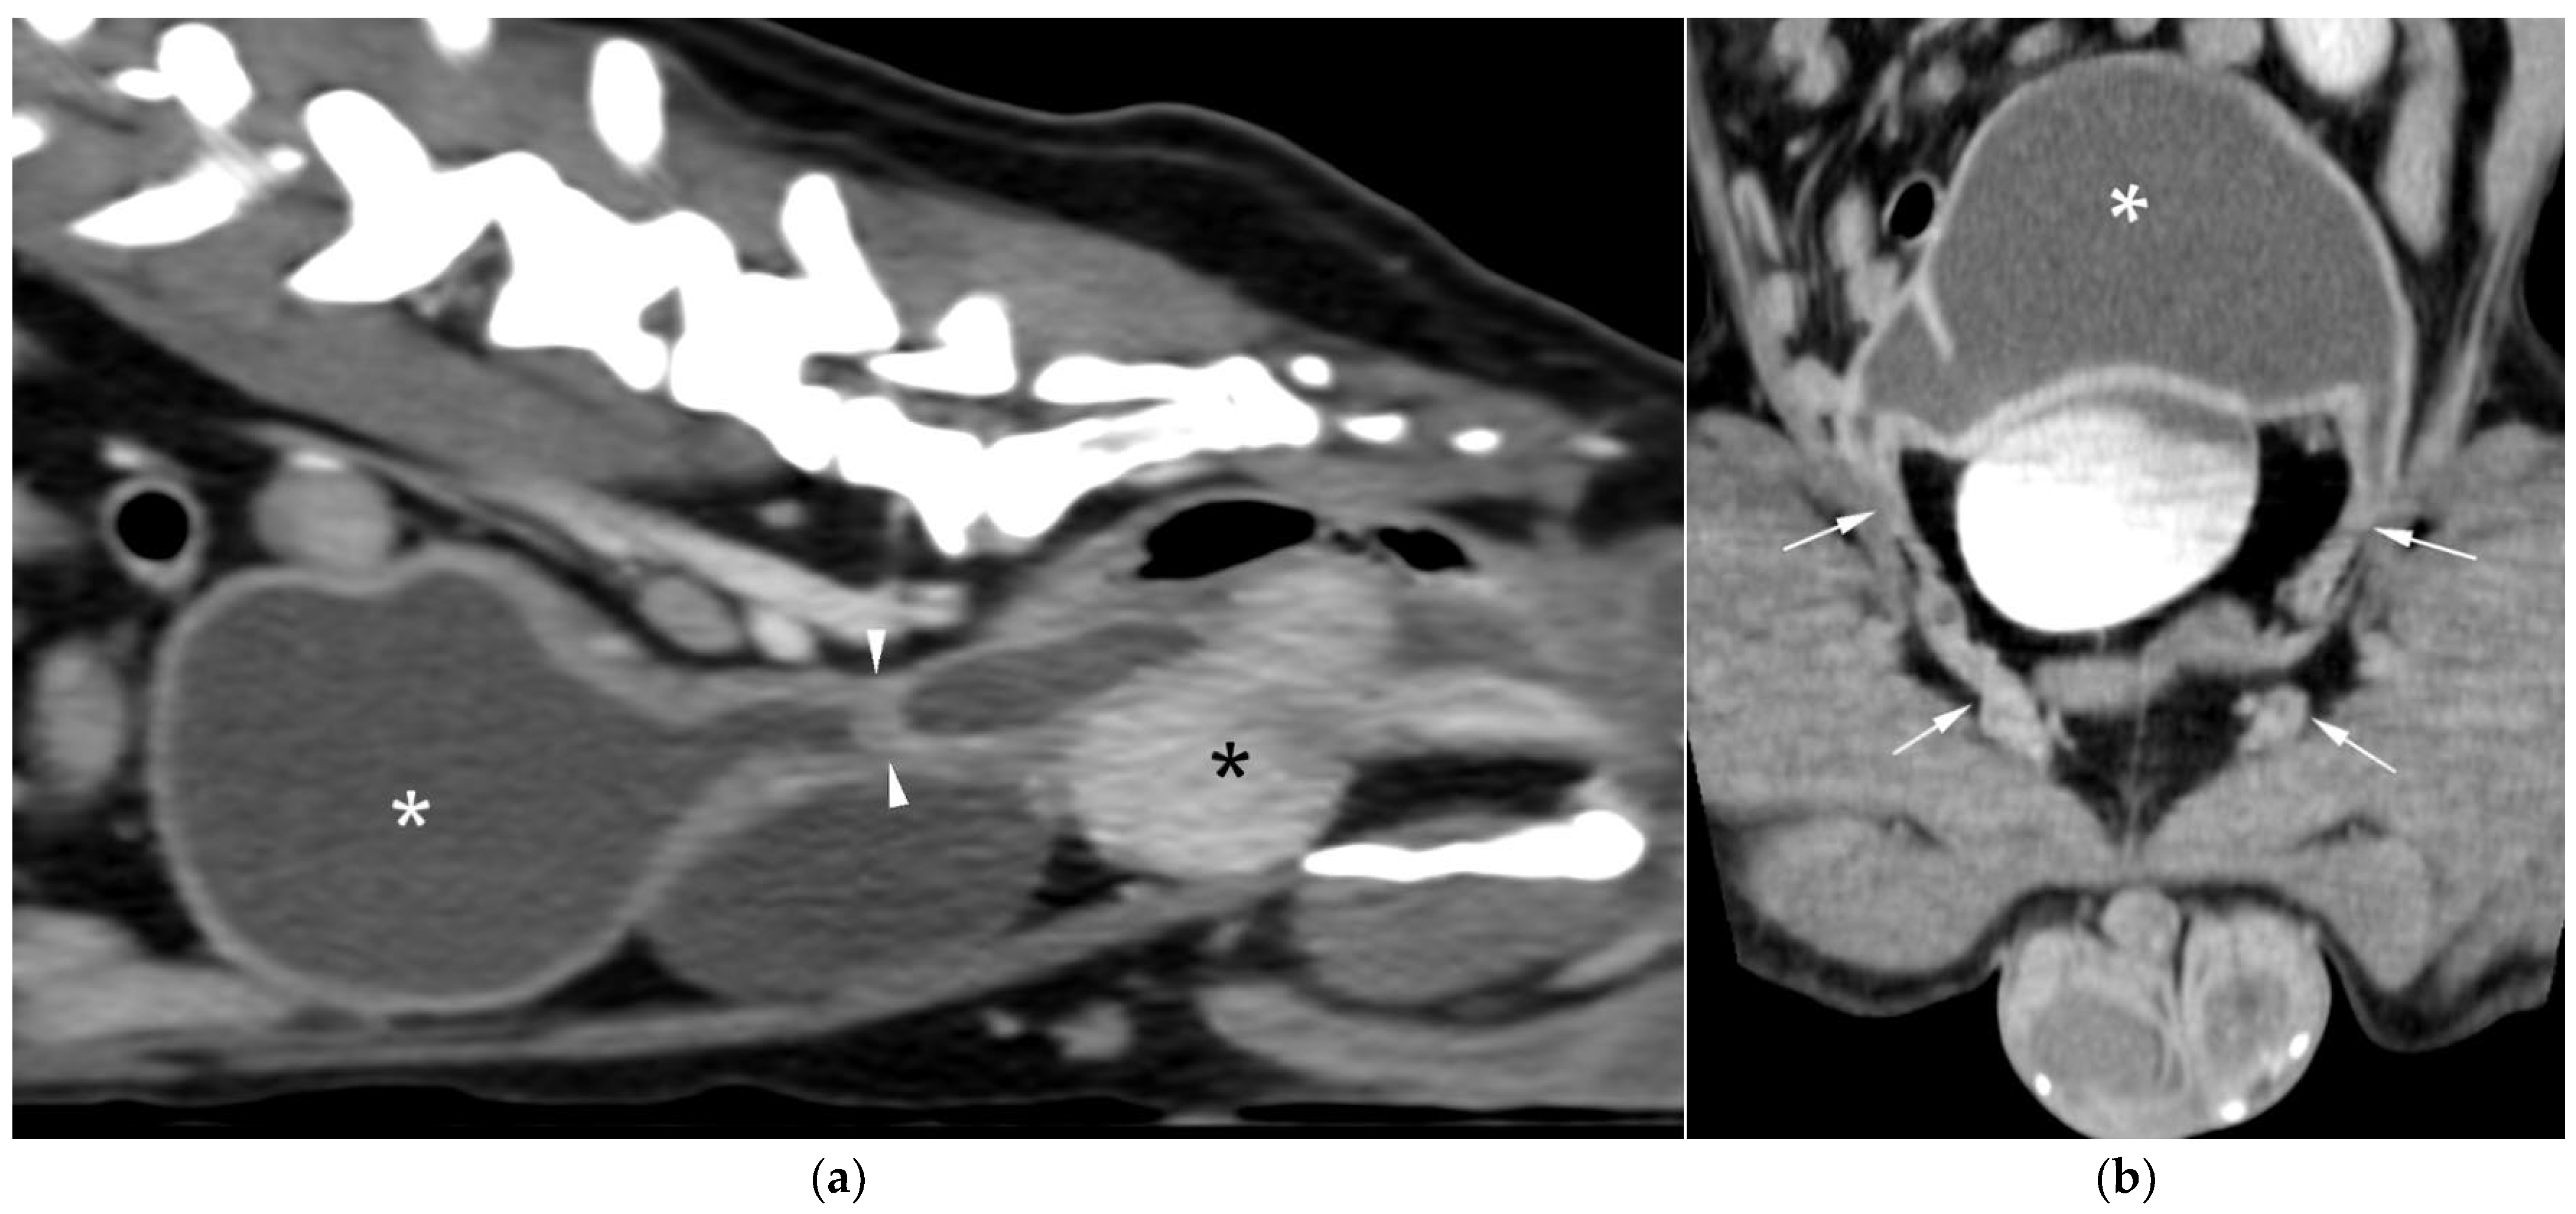

CT revealed a large cavitary structure arising from the craniodorsal aspect of the prostate and extending cranially through the mid-abdomen in each dog (Figure 4a, Figure 5a and Figure 6a). In cases 1 and 2, the structure consisted of a large central cavity, with bilateral horns, coursing caudally through the inguinal rings to each scrotal testis (Figure 4b and Figure 5b). The horns were fluid distended, except for the right horn in case 2, in which no lumen could be identified. In case 3, a Y-shaped bicornuate structure was identified (Figure 6a); the right horn terminated in a cranial peritoneal mass, while the left one ended in the mid-caudal abdomen.

In case 1, both testes were heterogeneous with irregular, ill-defined multifocal lesions after contrast; in case 2, a nodule was present in the left testis. In case 3, in continuation with the cranial end of the right uterine horn and intimately associated with engorged right gonadal vessels, a large, irregular, heterogeneous mass with moderate contrast enhancement was identified, causing a regional mass effect (Figure 6b). No structures compatible with a left gonad were detected in case 3, consistent with the previous unilateral orchiectomy.

Additional findings in all cases included: an enlarged, heterogeneous prostate with small hypoattenuating foci after contrast administration; free peritoneal fluid (moderate in case 2, mild in cases 1 and 3); and iliosacral lymphadenomegaly (moderate in cases 2 and 3, mild in case 1). Enlarged mammary glands and nipples were also noted in case 3.

Figure 6. CT of case 3 (a) Dorsal oblique view showing the UM (asterisk) on the right, with a cervix-like mural narrowing (arrows) and cranially extending paired uterine horns. The urinary bladder is positioned to the left, and the prostate lies caudal to them; (b) Parasagittal view demonstrating a large right-sided cranial peritoneal mass (arrowheads) with multiple sections of the UM (asterisks) caudal to the mass.